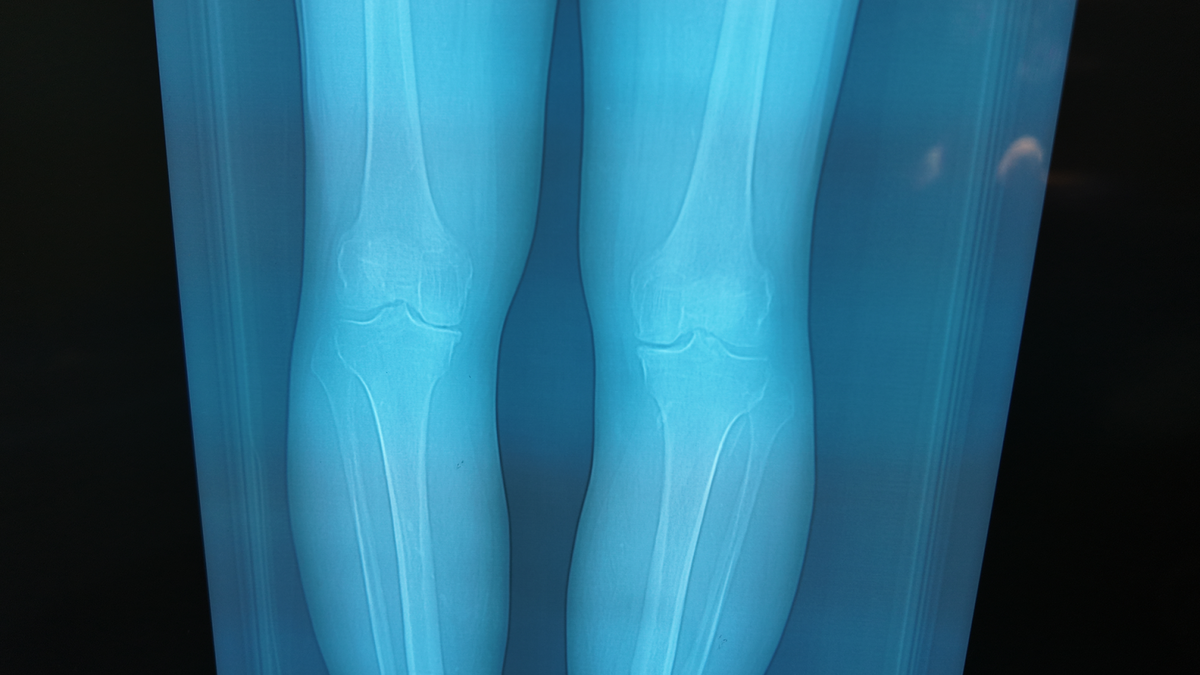

Диагностика: когда решение становится очевидным

После очной консультации и анализа снимков (рентген, МРТ) стало ясно:

речь идёт о

прогрессирующем артрозе коленного сустава.